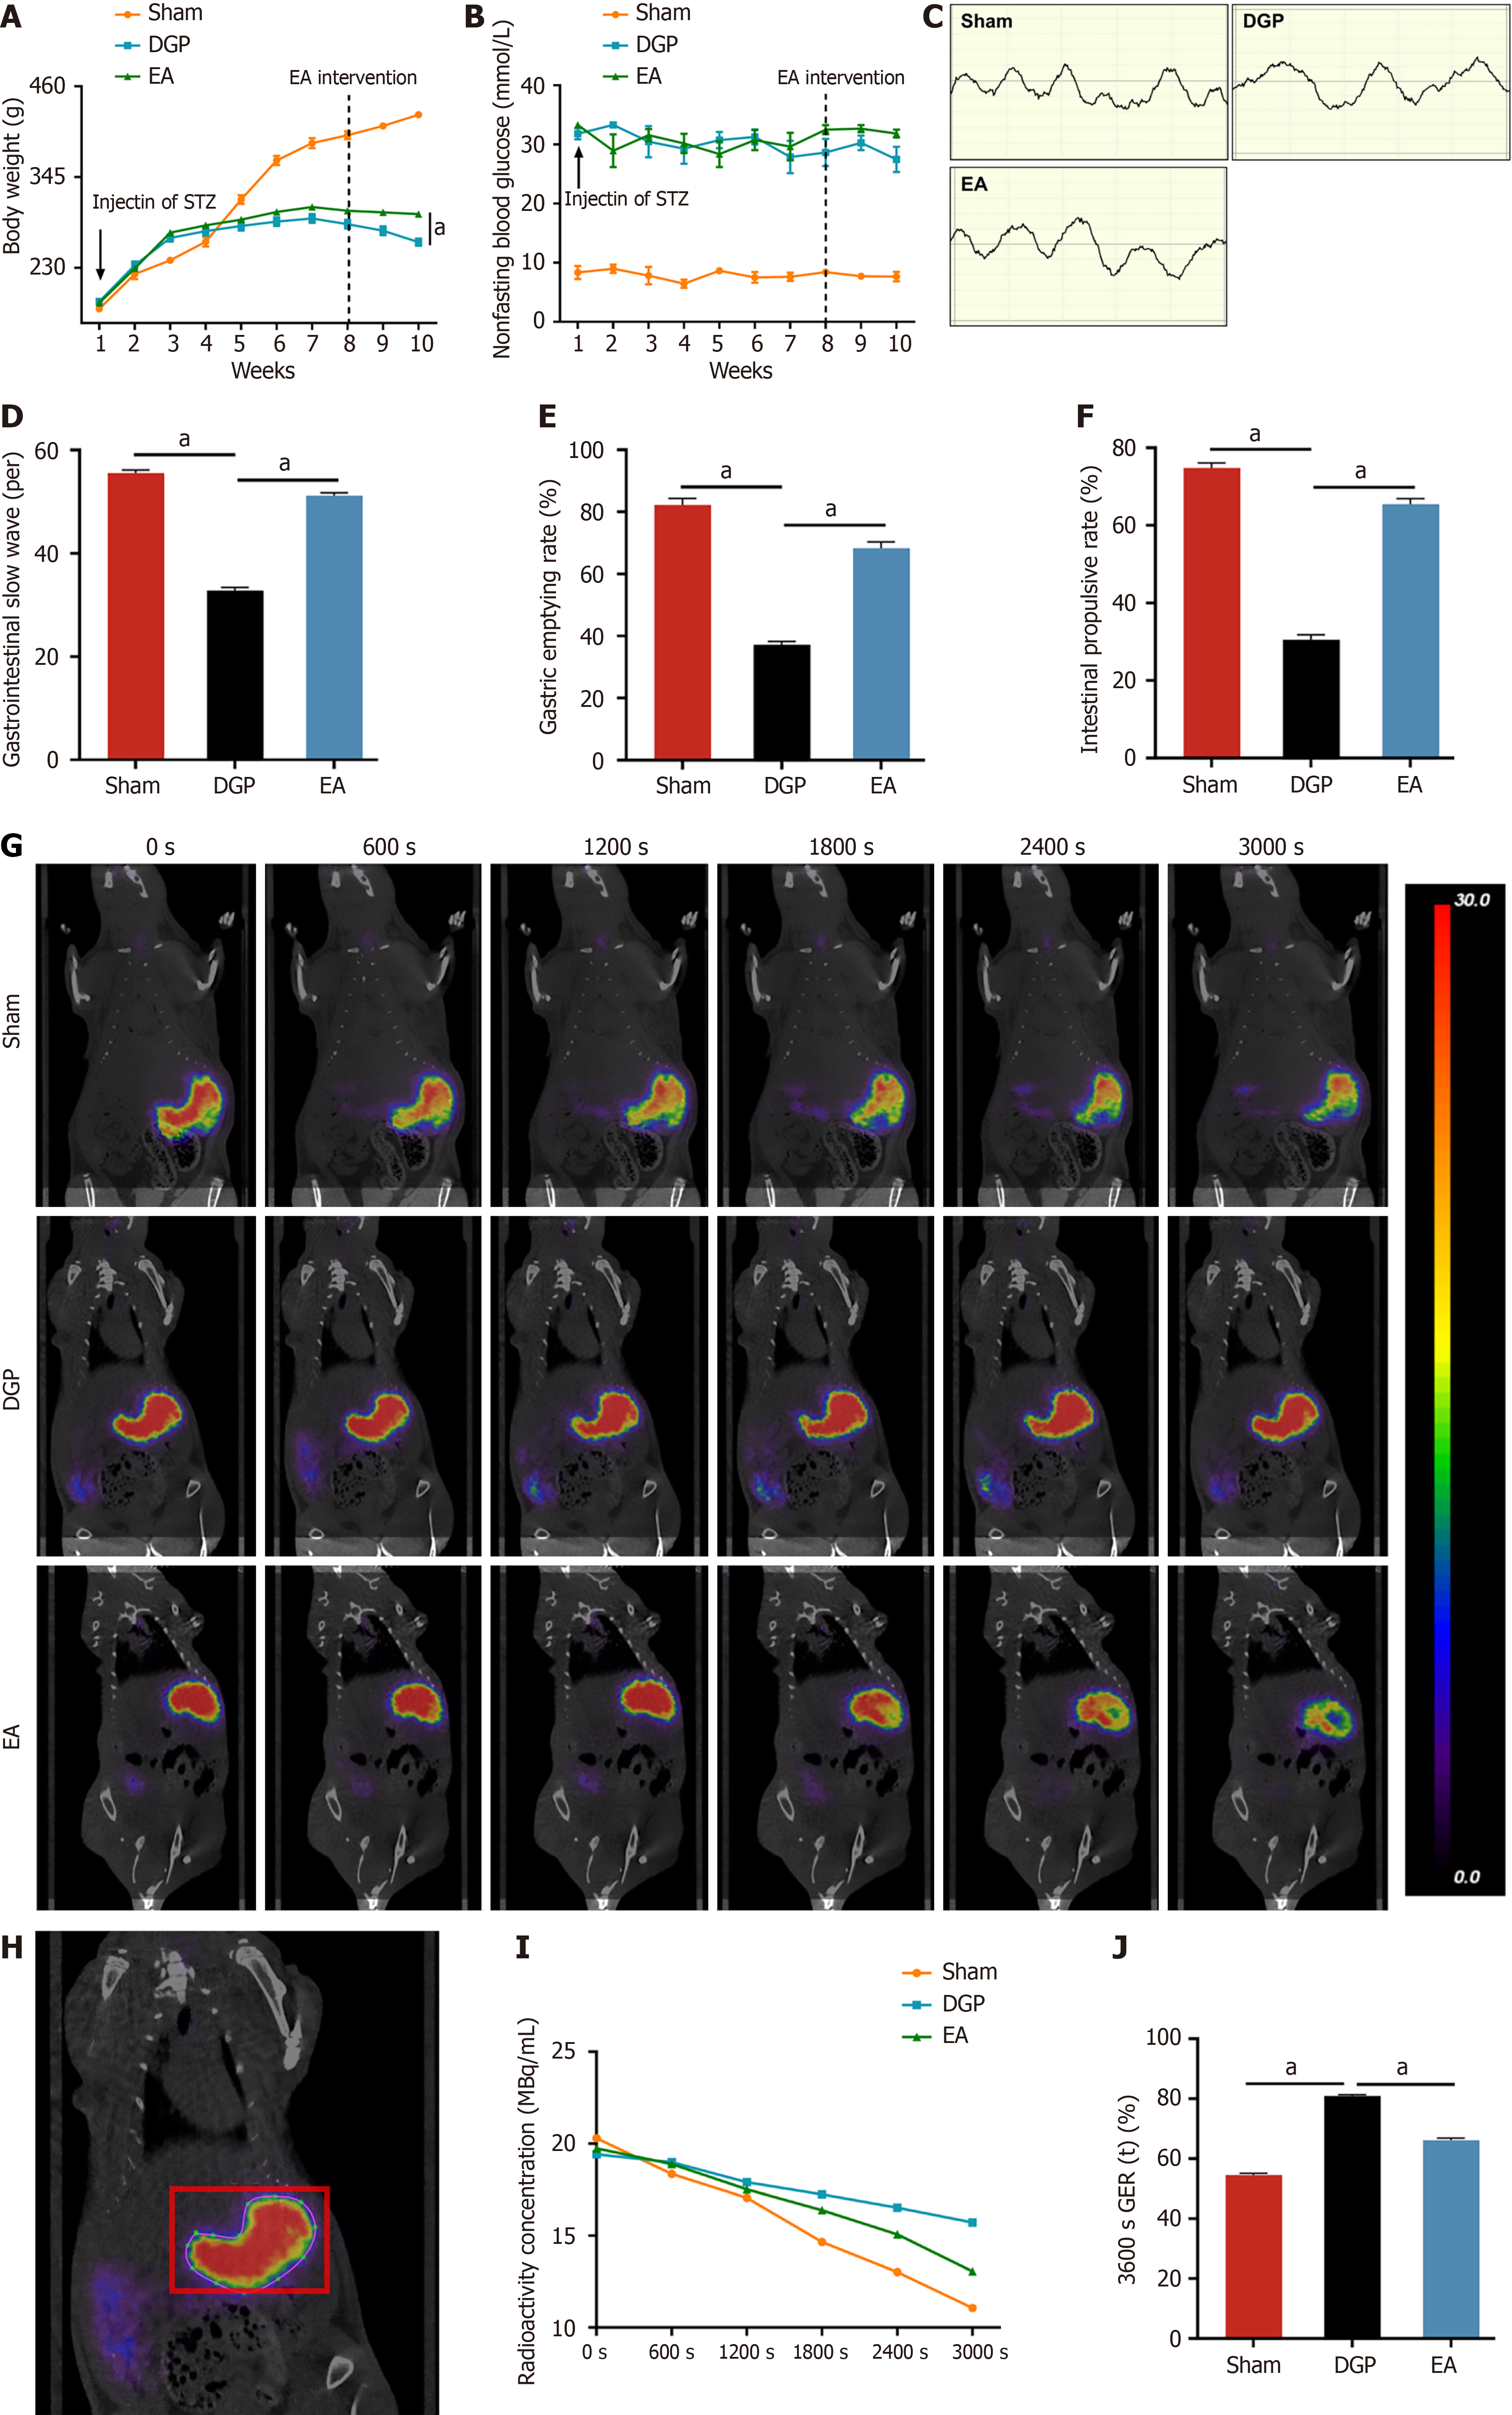

Longitudinal weight monitoring was conducted to evaluate diabetes-associated body weight dynamics (Figure 1A). The Sham group demonstrated progressive weight gain throughout the 10-week study period. In contrast, the STZ-induced diabetic rats (DGP and EA groups) demonstrated a less pronounced weight gain trajectory post-diabetes induction (week 1). The intervention of EA at week 8 led to a significant mitigation of diabetes-related weight loss, with the final body mass of EA-treated rats being 11.4% higher than that of the DGP controls at week 10 (P < 0.05). Metabolic profiling confirmed sustained hyperglycaemia (> 16.7 mmol/L, non-fasting) in the DGP and EA groups, with no significant glucose modulation by EA treatment (Figure 1B). Gastric motility was assessed via electrogastrography (Figure 1C and D). In comparison to the Sham group, DGP rats exhibited significantly reduced gastric slow wave discharges (P < 0.05), while EA intervention restored slow wave frequency to near-normal levels (P < 0.05). Further functional assessments revealed impaired gastric emptying and intestinal propulsion in DGP rats (P < 0.05), both of which were significantly improved by EA (P < 0.05) (Figure 1E and F). Furthermore, the gold standard for diagnosing DGP rats was employed to assess the efficacy of EA through the use of confirmatory PET-CT imaging with quantitative contrast tracking[11]. This revealed that EA-treated rats exhibited accelerated gastric emptying, with only 66.1% radioactivity remaining at 3600 seconds post-administration, in comparison to 80.9% in DGP and 54.5% in Sham controls (P < 0.05; Figure 1G-J). This multimodal validation, encompassing electrophysiological, functional, and imaging modalities, provides substantial evidence supporting the efficacy of EA as a robust intervention for restoring gastric motility in DGP.